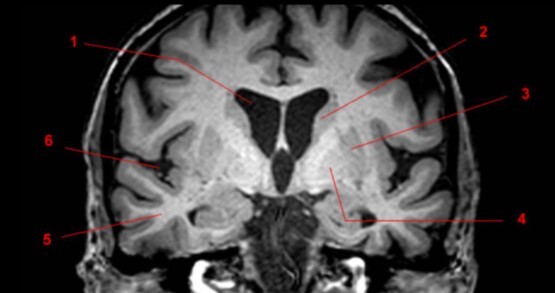

Q

Label 1-6

A

1=Frontal bone

2-Falx cerebri

3-Left frontal lobe

4-Left anterior cerebral artery

5-Right temporal lobe

6-Temporal horn of left lateral ventricle

21

Label 7-11

7=Basilar artery

8-Right posterior cerebral artery

9-Internal occipital protuberance

10-Midbrain

11-4th ventricle